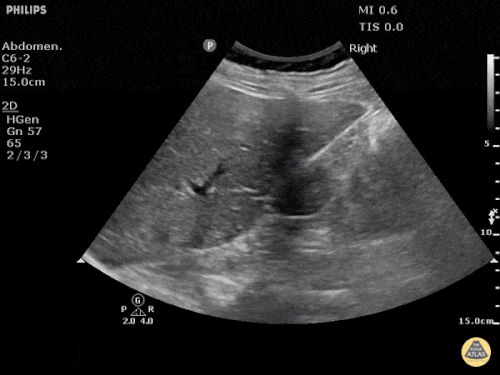

Based on the ultrasound image above, which shock etiology is most likely?

1 pts